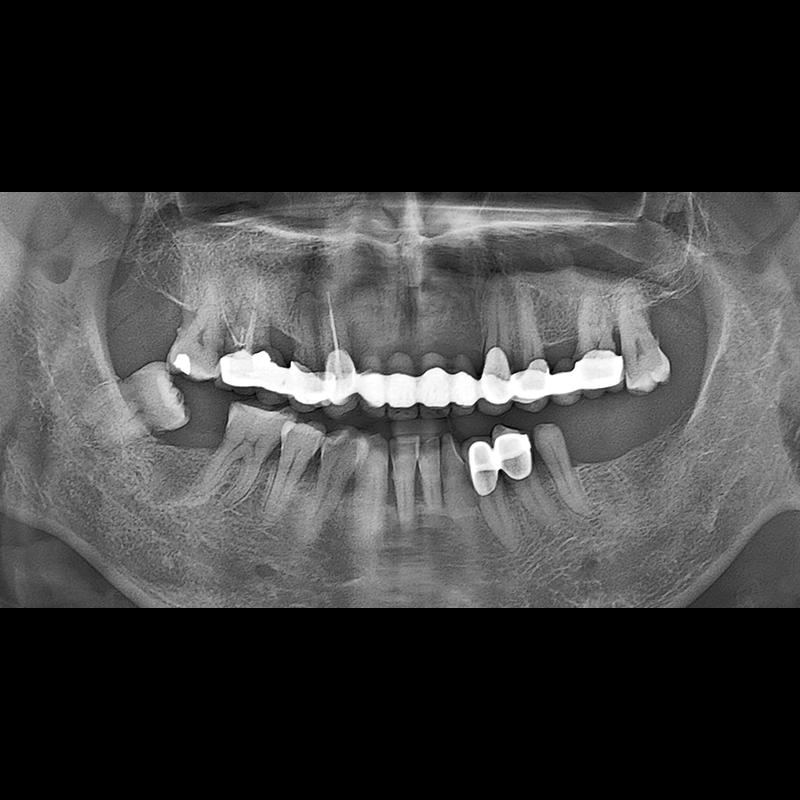

IMPLANT

BEFORE AFTER

种植牙前后的照片 2025.05.30

在缺失的牙齿部分和难以挽救的牙齿位置植入了种植牙。